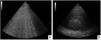

Imágenes de tóraxEl criterio imagenológico debe incluir infiltrados bilaterales en las Rx o TAC de tórax. Adicionalmente, en esta actualización se incorpora la ecografía pulmonar (evidencia de líneas B o consolidación (fig. 2 A y B). Cualquiera sea la modalidad empleada, debe sugerir pérdida de la aireación no totalmente explicada por colapso lobar, nódulos pulmonares o derrame pleural.

Para la nueva definición global de SDRA se incorporó a la ecografía para detectar la pérdida de aireación, en especial cuando no se encuentra disponible la Rx de tórax o la TAC. La ecografía pulmonar es especialmente útil cuando el operador se encuentra capacitado para la detección de consolidaciones bilaterales y edema pulmonar no cardiogénico, que es lo sugerido por esta definición. En el caso de la definición modificada para países con recursos escasos, la falta de pericia del operador podría conducir al aumento del sobrediagnóstico del SDRA, ya que se elimina la PEEP como criterio diagnóstico.

Si bien el uso de la ecografía pulmonar para este fin podría ser cuestionado, existe evidencia que la sustenta como un muy buen complemento para el diagnóstico imagenológico de SDRA32. Por otro lado, en un estudio muy reciente, se evalúo el score de edema pulmonar (LUS) para el diagnóstico de SDRA. En este estudio multicéntrico se demostró, a través de un modelo luego aplicado exitosamente a una cohorte de validación, que posee una muy buena capacidad diagnóstica, y que podría detectar el SDRA correctamente con un rendimiento comparable a evaluadores expertos de imágenes, e incluso con mayor precisión diagnóstica. Si bien se requiere validación en un mayor número de pacientes, representa un excelente punto de partida23.